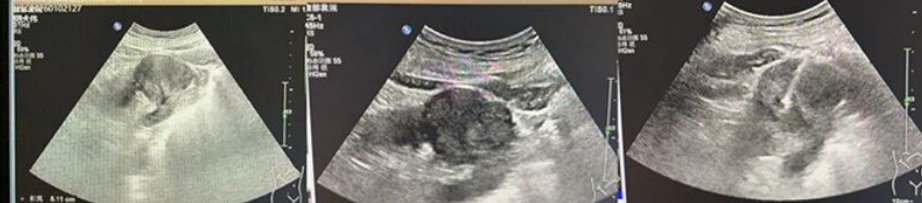

接诊医生详细询问病史后,为其安排腹部超声检查,在右肾中段发现一处向外凸起的不均质低实性回声,大小约5.1×4.3cm,形态欠规则、边界尚清,CDFI显示病灶内可见低速低阻型动脉血流信号,超声提示右肾占位、考虑恶性,建议进一步行超声引导下肾肿物穿刺活检明确性质。次日,我院为范大爷完成穿刺活检,病理结果确诊为肾透明细胞癌,结合腰椎CT检查,最终诊断为肾透明细胞癌伴腰椎转移。